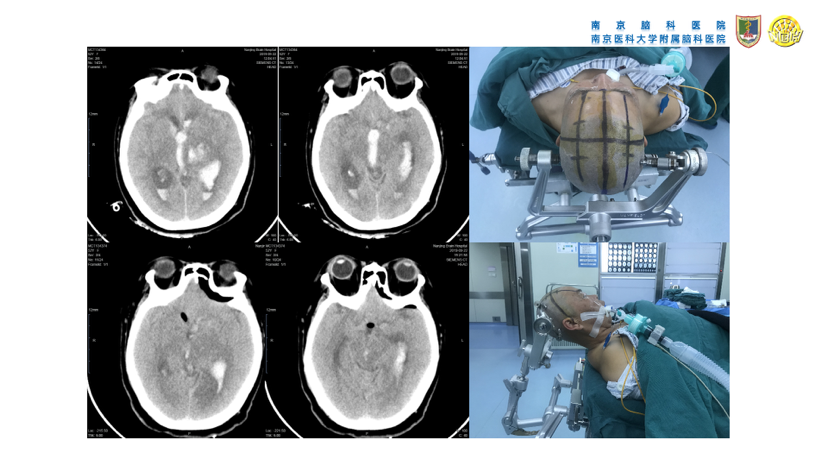

高血压性脑出血的微创手术治疗(高血压性脑出血的血压管理、镇静镇痛处理、手术指征、手术方法等重要问题)